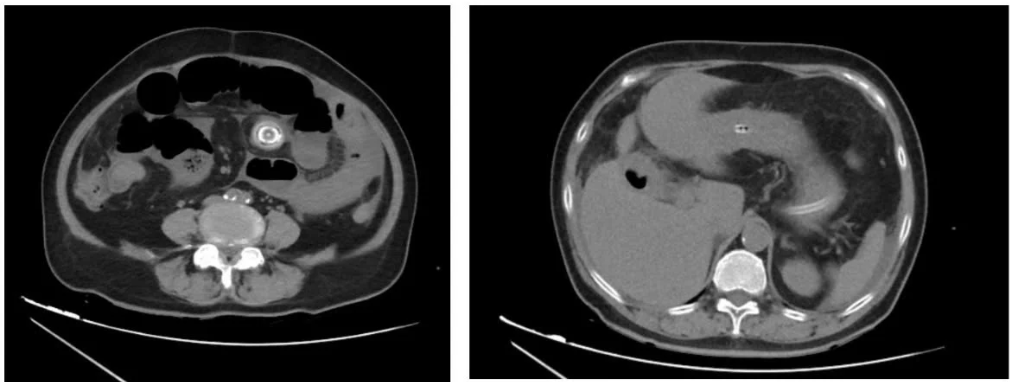

Hình ảnh sỏi mật của bệnh nhân qua chụp X.quang. Ảnh BVCC

Theo bác sĩ Vinh, tắc ruột do sỏi túi mật (gallstone ileus) là một trong những nguyên nhân hiếm gặp của tắc ruột cơ học. Biến chứng này xảy ra khi sỏi túi mật lâu ngày không điều trị gây viêm thủng túi mật vào tá tràng, sỏi di chuyển qua đường rò này xuống ruột và gây tắc nghẽn, chủ yếu ở hồi tràng của ruột non.